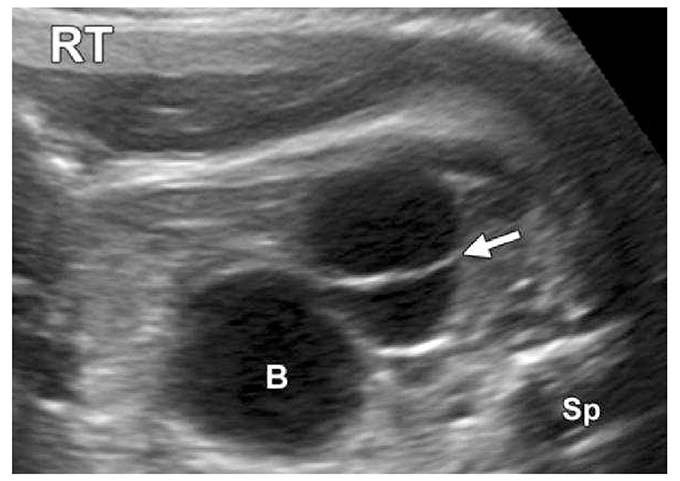

Hình ảnh nang buồng trứng thường xuất hiện trong quý 3 ở thai trẻ gái